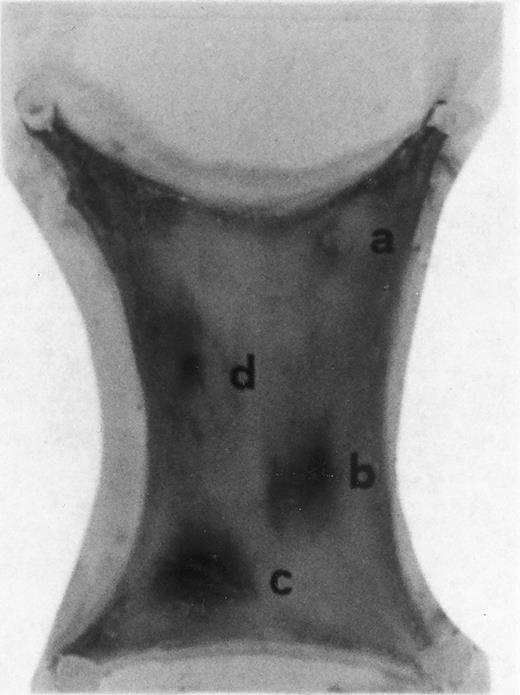

Evan's blue-stained intradermal injection sites showing the kinetics of the dermal inflammatory response to exogenous human recombinant RANTES 20 ng/50 μL (no. 2) and 10 ng/50 μL (no. 3); while PBS 50 μL was a negative control (no. 1) and LPS 10 ng/50 μL is a positive control (no. 4). This representative experiment was found to be reproducible and has been performed at least three times.

In Fig 2 we show the histologic results of a representative experiment (N = 12 rats) 4 hours after intradermal injection (50 μL) of LPS (10 ng), RANTES 20 and 10 ng, and PBS (control). This figure shows that while PBS (injection site no. 1) does not produce any appreciable effect, LPS (10 ng/50 μL, injection site no. 4) and RANTES (20 ng, site no. 2; and 10 ng, site no. 3) produced a marked enlargement of dye effusion.